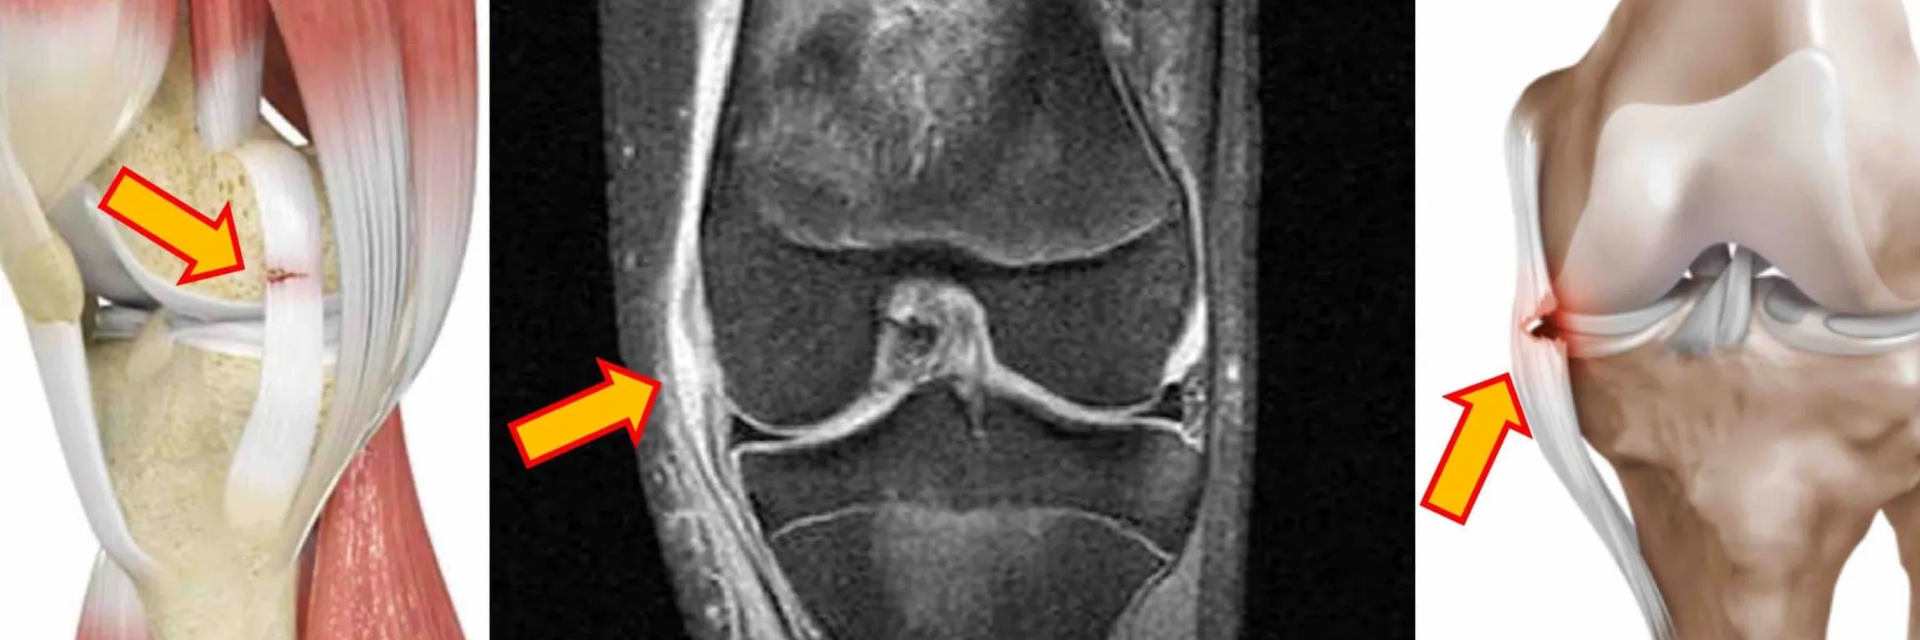

Un diagnóstico preciso es crucial para tratar la tendinitis del ligamento colateral medial.

Aquí se incluyen varios métodos:

- Historia clínica: Tu fisioterapeuta primero te preguntará sobre tus síntomas y actividades recientes.

- Examen físico: Te pedirá que muevas la rodilla y buscará puntos de dolor o sensibilidad.

- Pruebas de imagen: En algunos casos, se pueden utilizar radiografías, resonancias magnéticas o ecografías para identificar la inflamación específica del LCM.